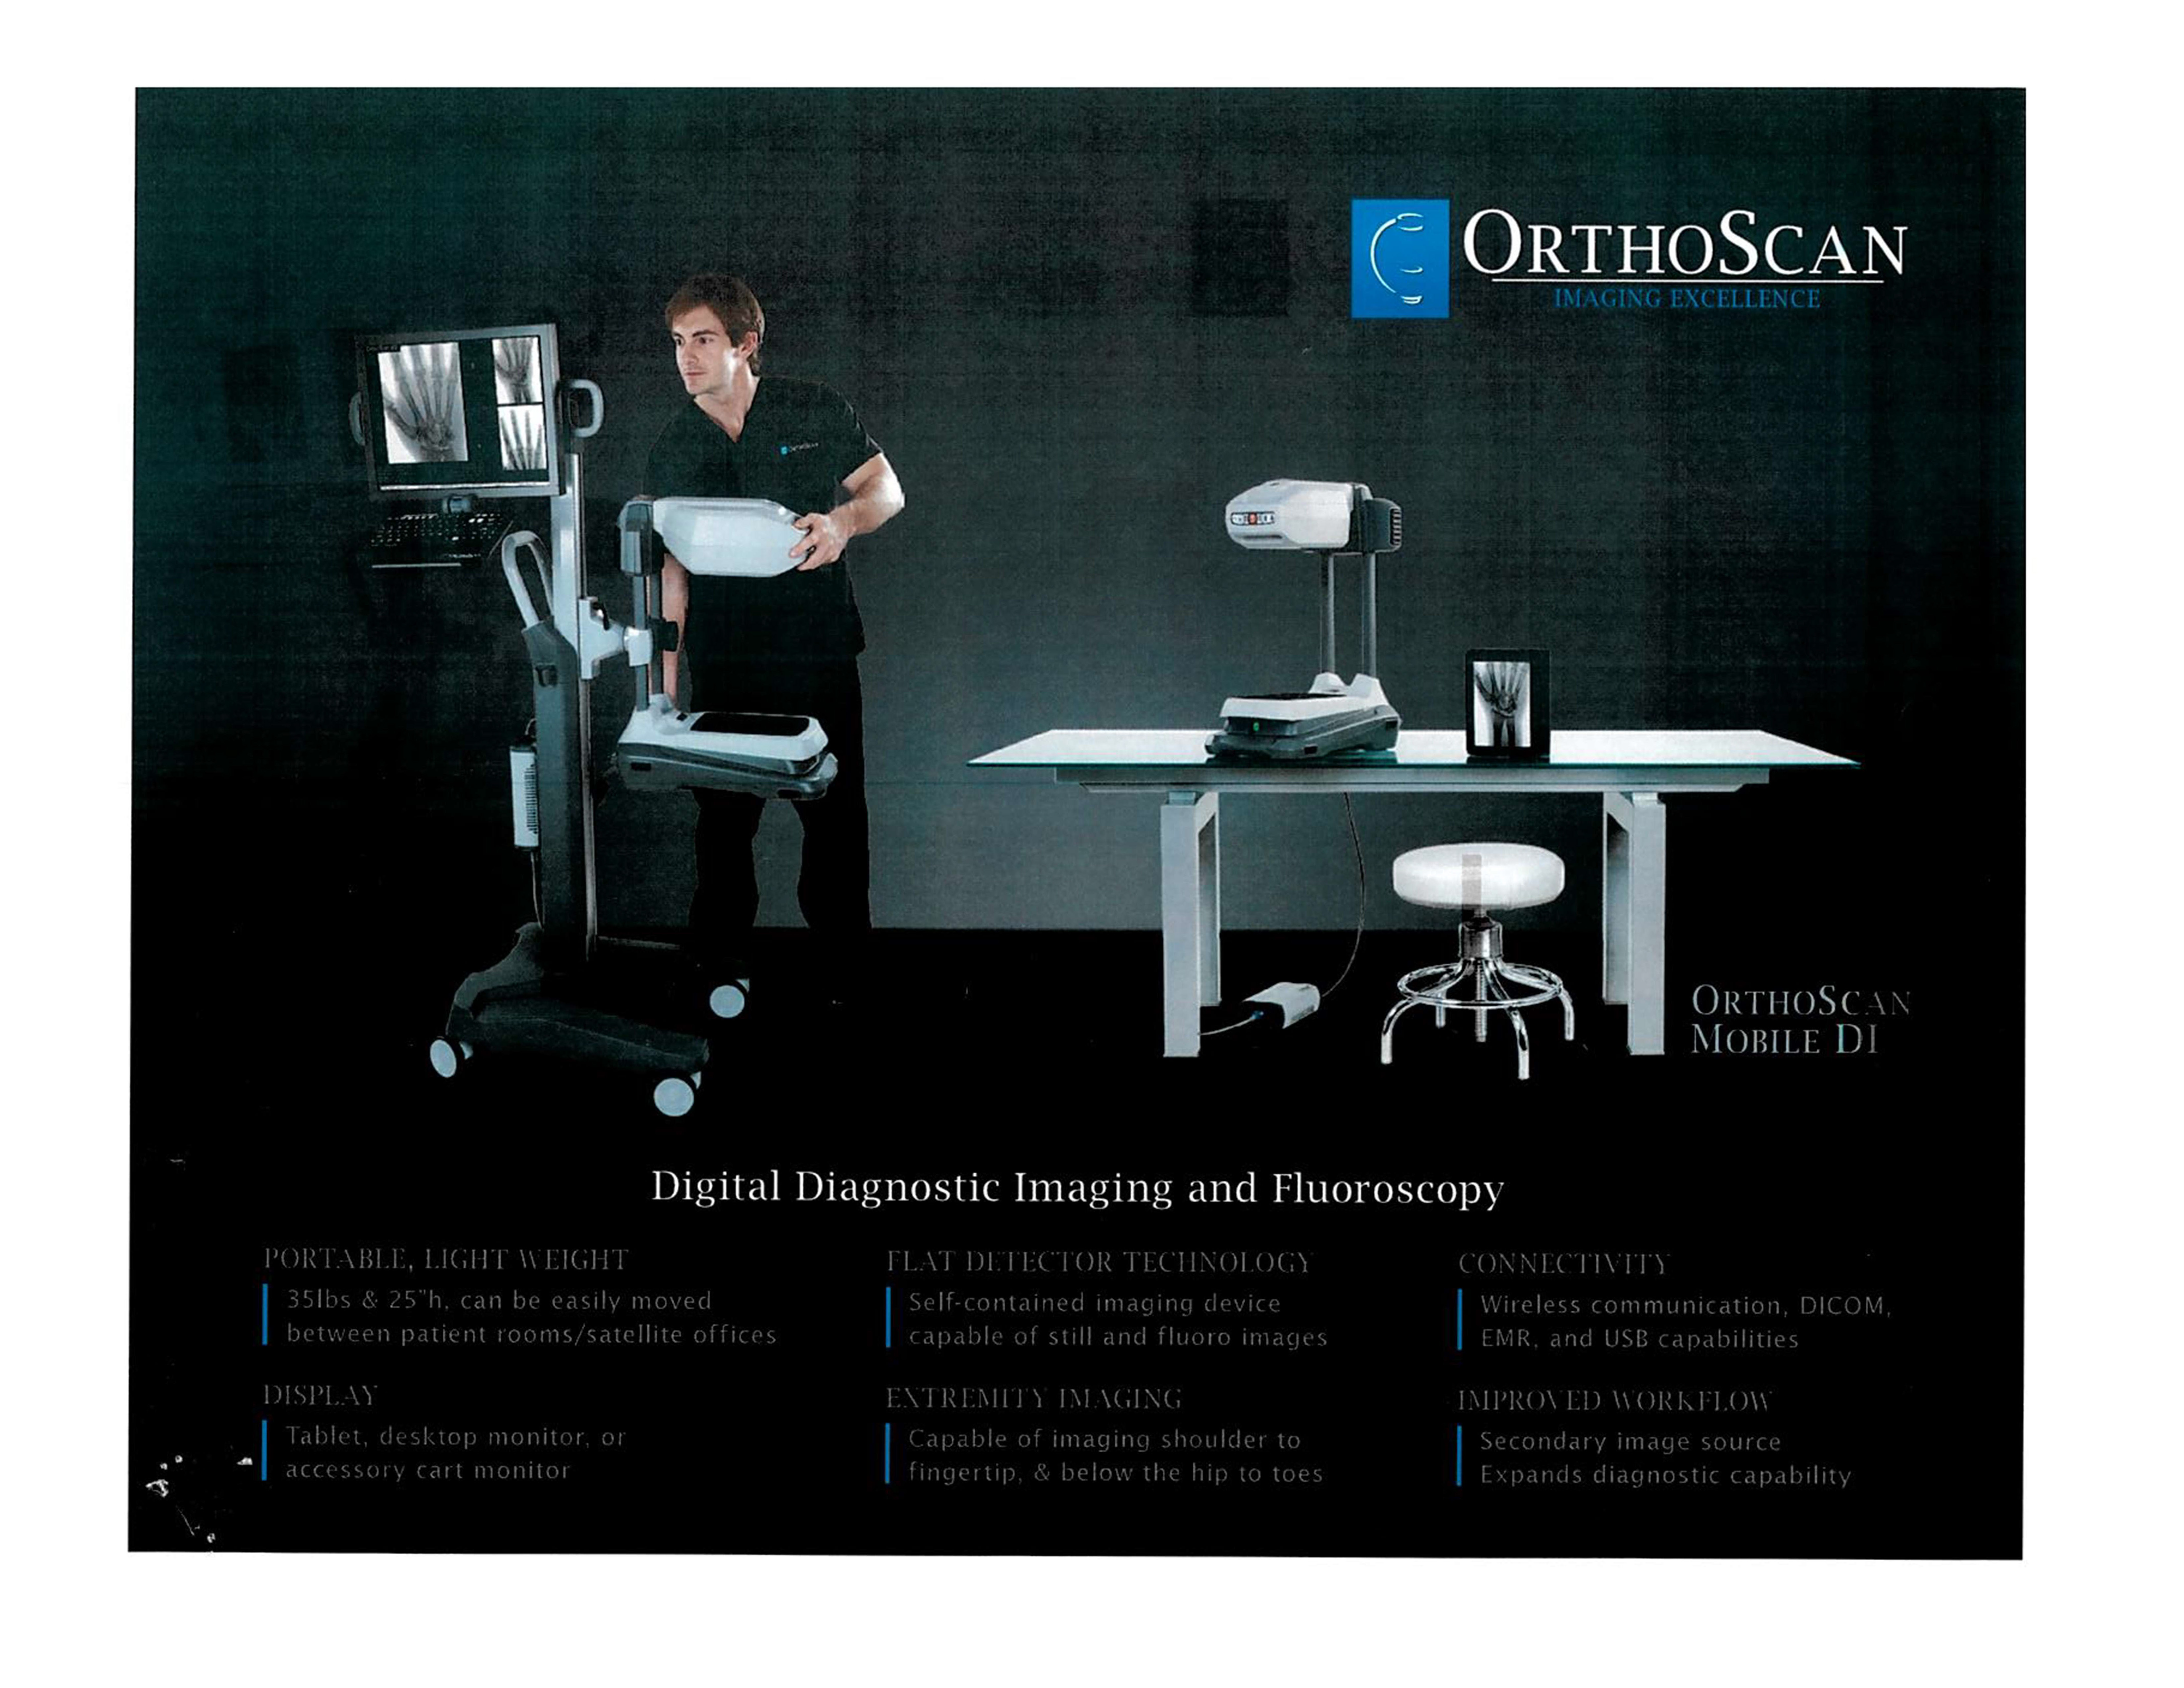

The Advanced Arthritis Relief Program (AARP) is a knee osteoarthritis (OA) treatment system that consists of fluoroscopic guided injections of Hyaluronic Acid, targeted Physical Therapy, and a special uploading Knee Brace. It’s MD, MP, and PA approved and covered by all major insurance carriers as well as Medicare.